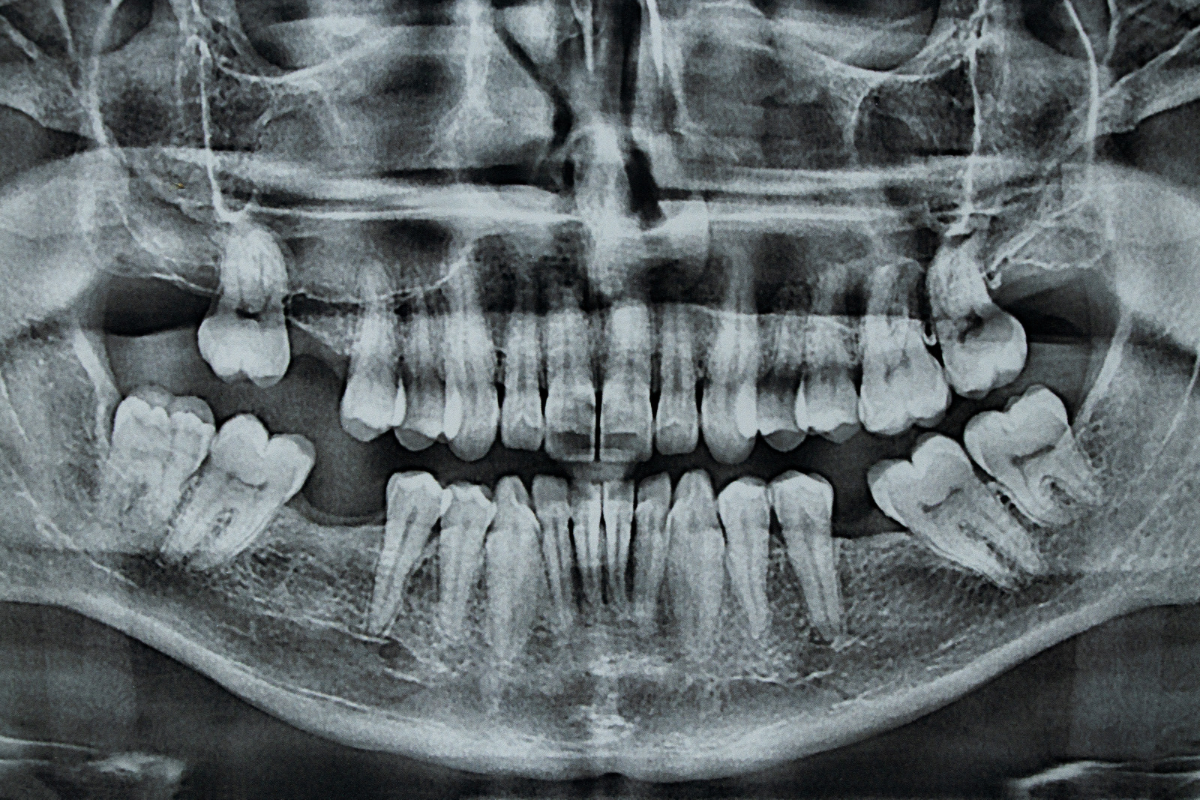

OPG – panoramatický rentgen

Celkový snímek čelistí, zubů, kloubů a anatomických struktur.